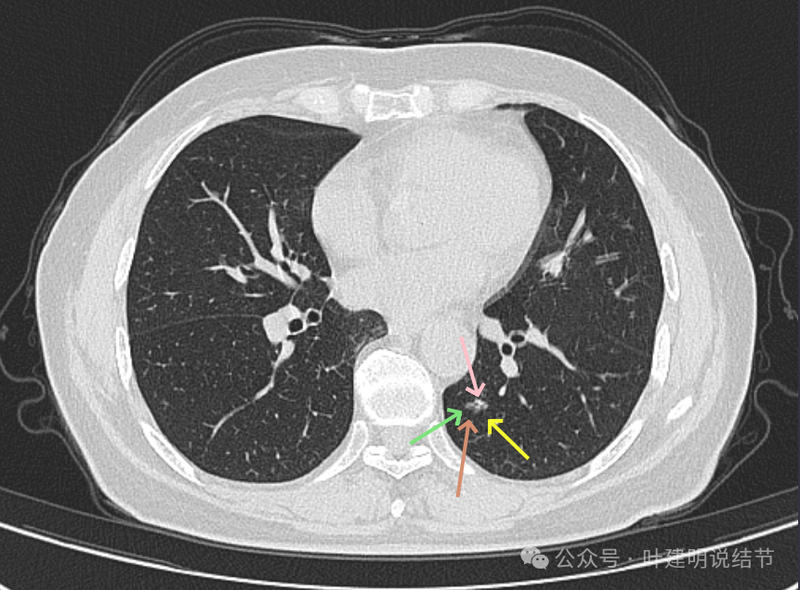

混合密度,轮廓清。有实性成分、有局部细支气管扩张、有浅分叶征,病灶有明显磨玻璃成分。